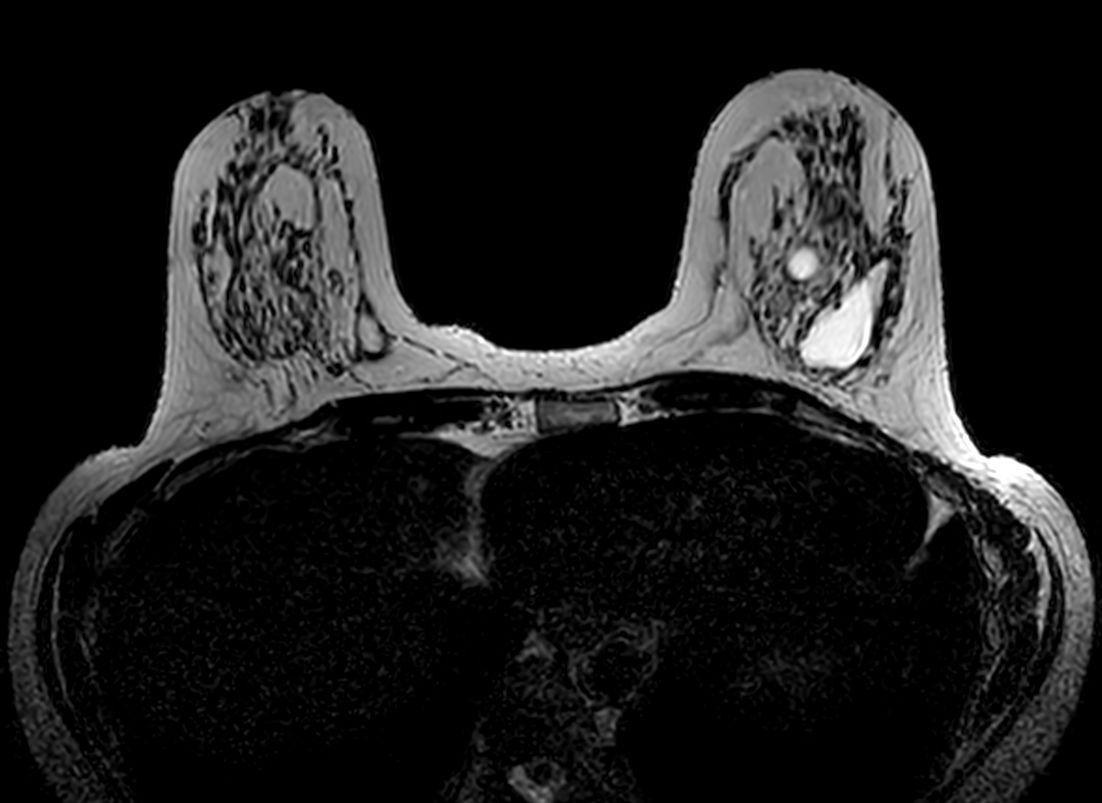

Axial 3D VANE XD

3D VANE XD (coronal reformat)

3D VANE XD (sagital reformat)

3D Breast imaging lets you acquire high resolution data in multiple directions, including oblique, in one scan helping you enhance your confidence when diagnosing lesions. 4D FreeBreathing provides dynamic information with a high temporal resolution, allowing contrast-enhanced MRI breast studies.